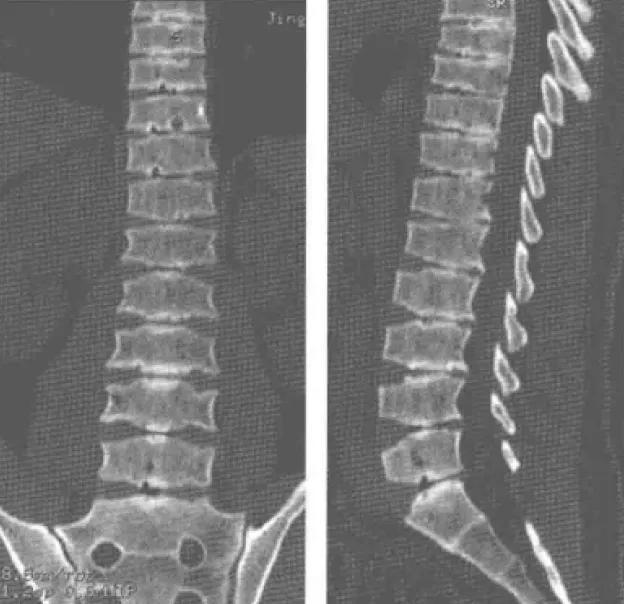

晚发型脊椎骨骺发育不良( spondyloepiphysealdysplasia tarda, SEDt)是一类累及脊椎椎体和骨骺的骨软骨发育不良性疾病,具有高度的遗传异质性。晚发型脊椎骨骺发育不良是由SEDL基因突变引起的罕见的X连锁隐性(XR)遗传病。临床上,主要表现为短躯干性侏儒,但智力正常,无头面部畸形。本病发病较晚,故称为晚发型脊椎骨骺发育不良。目前认为本病病因和发病机制可能为原胶原蛋白II 基因突变所致,该致病基因位于X染色体的短臂末端。X连锁晚发型脊椎骨骺发育不良通常是男性发病(图3-5-1、图3-5-2),女性只携带致病基因而表型正常。致病后软骨成骨受到影响,从而导致脊椎骨骺及长骨骨骺的不发育或发育落后,形成了短躯干侏儒的典型身材、脊椎骨的驼峰状改变。 本病均有不同程度腰背及髋、膝疼痛和活动受限。共同体征:颈短肩高,桶状胸,步态蹒跚,智力正常的短躯干型侏儒;血液生化检查均正常。身材矮小是本病临床特征之一,一方面由于软骨发育障碍,椎体变扁,椎间隙及关节间隙均变狭窄,造成患者身材矮小;另一方面,由于软骨发育障碍,软骨下骨化异常,造成骨发育受限。虽然本病的确切机制不详,但骨发育异常是本病患者身材矮小的另个 主要原因。影像表现1、 X线平片及CT表现脊椎表现,由于软骨发育不良的主要病理改变为软骨的过度增生和成熟障碍,造成关节软骨持续性退化、丢失和骨破坏,骨密度下降,其结果是长骨的骨端进行性膨大及骨质增生,关节间隙逐渐狭窄;椎体变扁,二次骨化中心形成障碍,从而影像上早期出现明显骨关节退行性改变,使椎体呈横置花瓶状和*弹子**头状改变,胸椎中段及腰椎明显,椎间隙明显变窄,脊柱侧弯。由于椎体软骨发育异常,椎间盘与椎体的连接不稳定,椎间盘容易发生疲劳损伤导致椎间盘变性,椎问隙变狭窄,椎体表面终板凹凸不平,并可出现多个凹陷切迹,为史莫结节改变,椎间隙内可出现低密度影( 真空征),双侧肋骨表现后肋窄小,前段宽呈飘带状,但椎弓根显示正常。

2. MRI表现除显示 上述形态改变外,椎体中后部上下缘呈驼峰状突起,脊椎骨呈驼峰状椎体表现,以腰段椎体明显。脊椎骨质表现为疏松信号,TIWI、T2WI呈低信号;椎间盘变薄,形态不规则并有不同程度向后突出,椎间盘纤维环和富髓核结构不能分辨, 椎间盘信号减低,T1WI、T2WI 均呈低信号;个别椎体终板可出现终板骨软骨炎改变; 胸、腰椎后纵韧带及 黄韧带不同程度增厚, 压迫硬膜囊及脊髓,椎管明显狭窄。